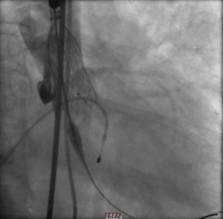

经过周密的筹备,3月5日上午,何贵新主任团队在广东省心血管病研究所罗建方教授团队的指导下,“临时起搏器植入、鞘管植入、跨瓣、球囊扩张、精准定位、瓣膜释放.......”,历经1小时余,顺利为韦奶奶行经导管主动脉瓣置换术(TAVR),置入新的主动脉瓣,打开心脏血液流出的第一道门,手术创口仅针眼大小。术后,复查超声心动图提示人工主动脉瓣膜工作良好,心脏血液泵出顺畅,术前跨瓣压差62 mmHg术后降至差2mmHg,手术非常成功,术后第2天即可下床活动。